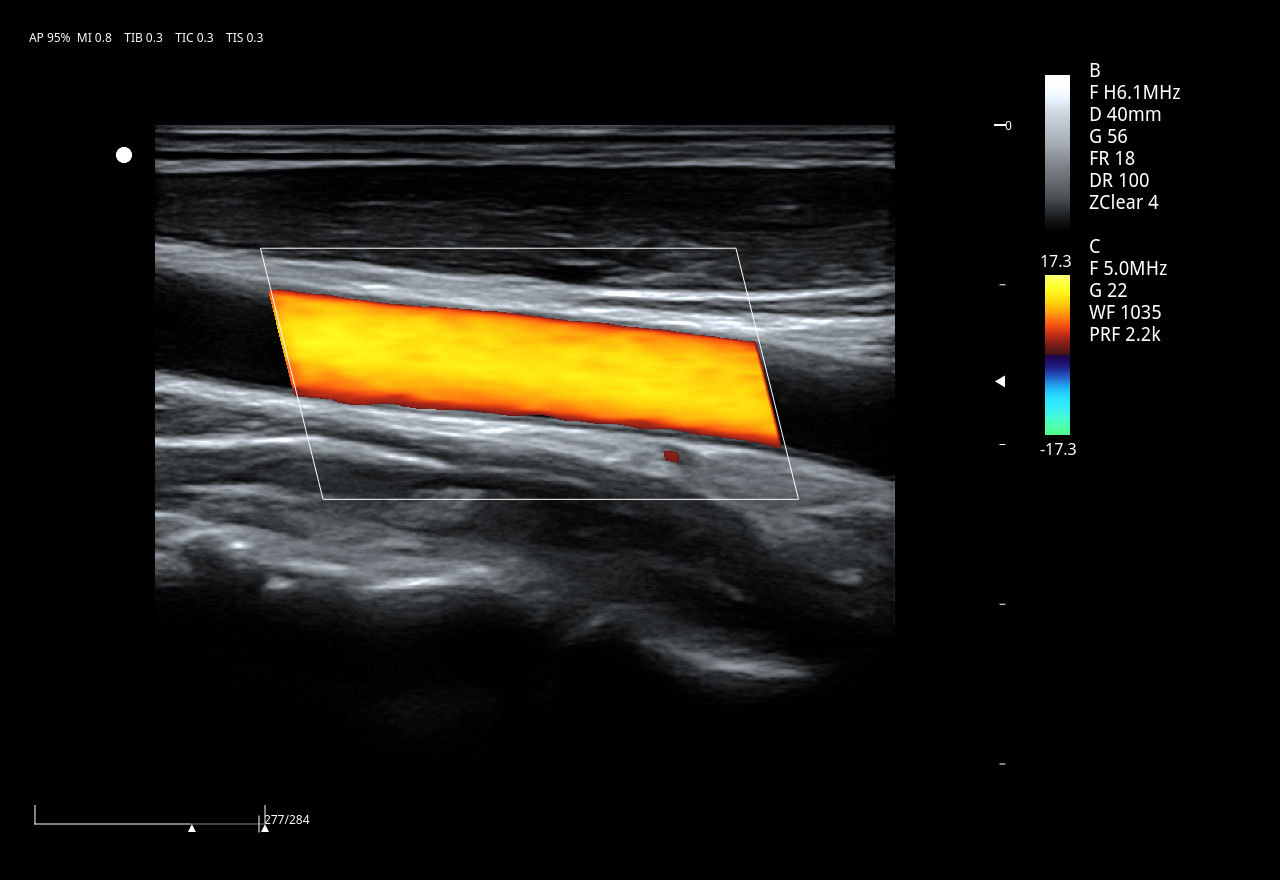

El Doppler Color ViV 20 es un ecógrafo de nueva generación diseñado para ofrecer una experiencia clínica superior con un equilibrio perfecto entre rendimiento, durabilidad y accesibilidad. Su arquitectura avanzada proporciona imágenes claras y precisas, permitiendo diagnósticos confiables en aplicaciones como abdomen, ginecología, vascular, partes blandas y más.

Imágenes clínicas extraordinarias

| Aplicaciones | Cardiología, abdomen, vasos sanguíneos, estudios generales |